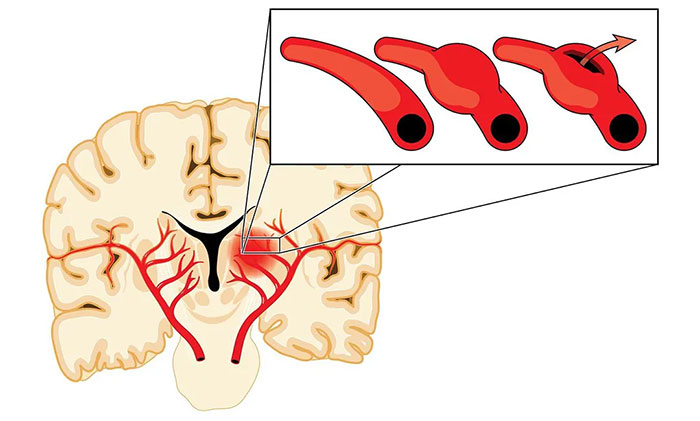

煙霧病的本質(zhì)是腦血管主干(頸內(nèi)動(dòng)脈和大腦中動(dòng)脈)的狹窄和閉塞,導(dǎo)致灌注異常,引起腦細(xì)胞缺血,同時(shí)又伴以代償性顱內(nèi)異常新生小血管。這些煙霧狀血管畢竟不是原始正常的血管,壁很薄,容易破裂出血,這就是煙霧病既容易引起腦梗死,又容易出血的原因。

手術(shù)則是目前最主要的煙霧病治療方式,可分為直接血運(yùn)重建術(shù)、間接血運(yùn)重建術(shù)以及聯(lián)合(直接+間接)血運(yùn)重建術(shù)。手術(shù)治療的目的,是使用來(lái)自頸外動(dòng)脈系統(tǒng)的血液供應(yīng)來(lái)增加顱內(nèi)血流,從而改善腦血流量和腦血流儲(chǔ)備能力。

“這就好比‘南水北調(diào)’,黃河水情不足時(shí),就從長(zhǎng)江引流,支援北地,緩解缺水局面。”宮衛(wèi)東主任形象地打了個(gè)比方,通過(guò)手術(shù)建立由腦外血管向腦內(nèi)供血的通路,改善腦內(nèi)血流。腦血供改善以后,對(duì)于煙霧狀血管的供血需求會(huì)逐漸減少,從而降低再次發(fā)生腦缺血和腦出血的風(fēng)險(xiǎn),改善患者的預(yù)后。

▲重建血運(yùn),“灌溉”缺血腦細(xì)胞